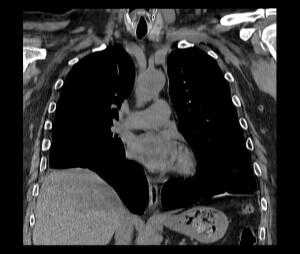

- Лучевая диагностика. Выполняется рентгенография и КТ грудной полости, КТ брюшной полости. Выявить разрыв на рентгенограмме можно только при пролапсе органов пищеварения в область грудной клетки. Для уточнения локализации травматического дефекта грудобрюшной перегородки, дифференциальной диагностики травмы и релаксации органа осуществляется контрастная рентгенография желудка либо ирригография. Просматривается желудок или петли кишечника в левой половине грудной клетки, определяется смещение пищевода.

КТ органов грудной клетки/брюшной полости. Травматический дефект в передних отделах диафрагмы справа с эвентрацией кишечника, сальника, кровеносных сосудов в грудную полость

КТ. Наиболее информативным методом исследования является компьютерная томография, дающая полную информацию о степени релаксации и характере изменений органов грудной и брюшной полостей. Во всех случаях релаксации, даже при небольшой ее выраженности, наблюдается ателектаз и воспалительные изменения базальных сегментов легкого. С внедрением компьютерной томографии практически отпала надобность в остальных традиционных методах дифференциальной диагностики.

Релаксация правого купола диафрагмы на КТ